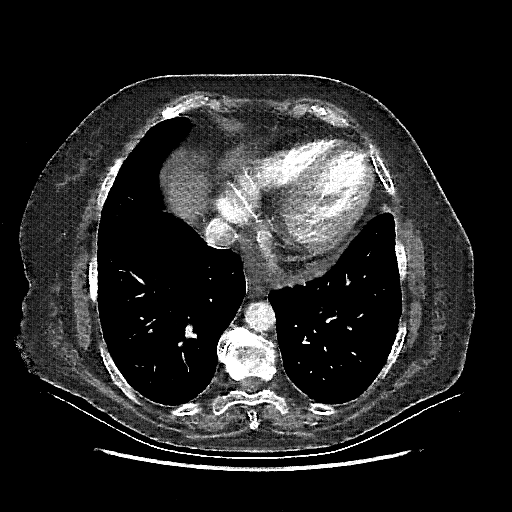

Original NATIVE CT scan (input)

Lung window (WL -600, WW 1500 β†’ Low βˆ’1350, High +150)

Reconstructed NATIVE CT scan (cycle consistency)

Original VENOUS CT scan

Generated VENOUS CT scan (A→B translation)